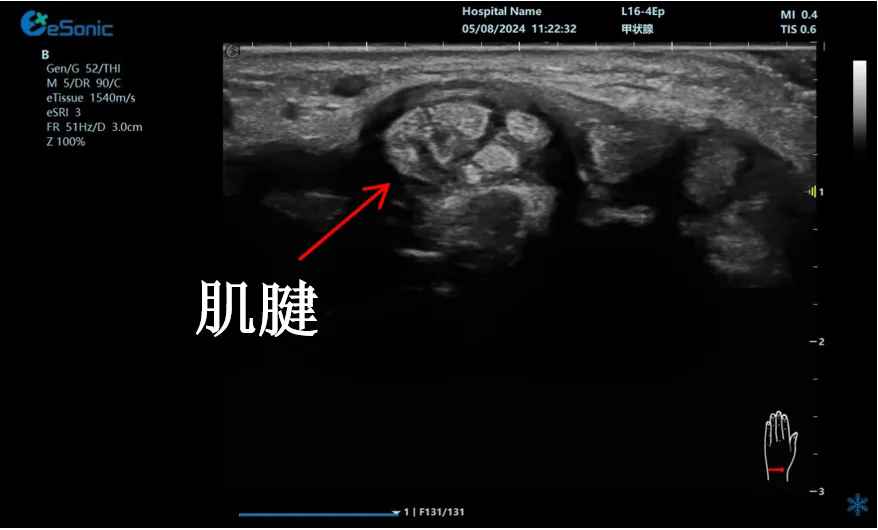

mFlow?技术在腱鞘炎诊疗中的应用

【背景】:左手腕关节第四腔室腱鞘炎。

【痛点】:普通彩色多普勒不敏感,只能看到细小点状血流,容易被忽略,难以进行分级诊断和疗效评估。

【方案】:利来国国际网站医疗(ESI)超微血流技术可以看到腔室内肌腱周围环状血流,可充分提示: